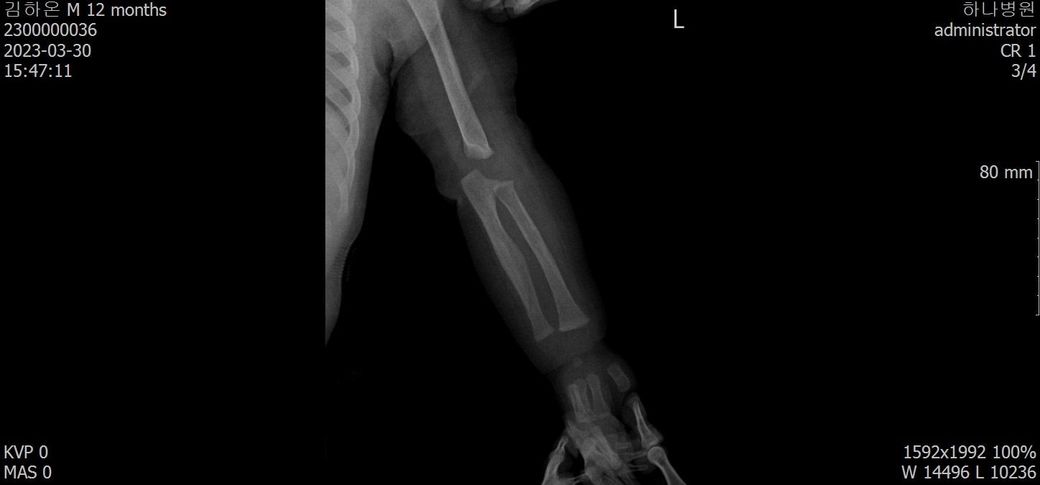

어떤 의사분 발언에 의하면 첨부된 4월 10일 x-ray사진처럼 유합직전의 다량의 칼러스가 발생되었다고 합니다.

아래에 3월 30일 x-ray 사진 2개, 4월 10일 X-ray 사진 2개 씩 첨부드립니다.

첨부된 사진에 X-raY 촬영 날짜가 기재되어 있습니다.

Dating fractures in infants, Clinical Radiology., Volume 66, Issue 11, November 2011, Pages 1049-1054 문헌을 보면 뚜렷한 가골 (callus)은 수상 20일쯤 확인되는걸 알 수 있습니다. 올려주신 사진을 보면 04.10에는 뚜렷한 가골이 관찰되기 때문에 20일 전인 03.20 이전일 거라고 예상이 됩니다. 03.30 X-ray에는 가골이 전혀 확인되지 않기 때문에 03.10 이후일 가능성이 높아보이고 03.10~03.20 사이가 가장 가능성이 높지 않을까 생각됩니다.